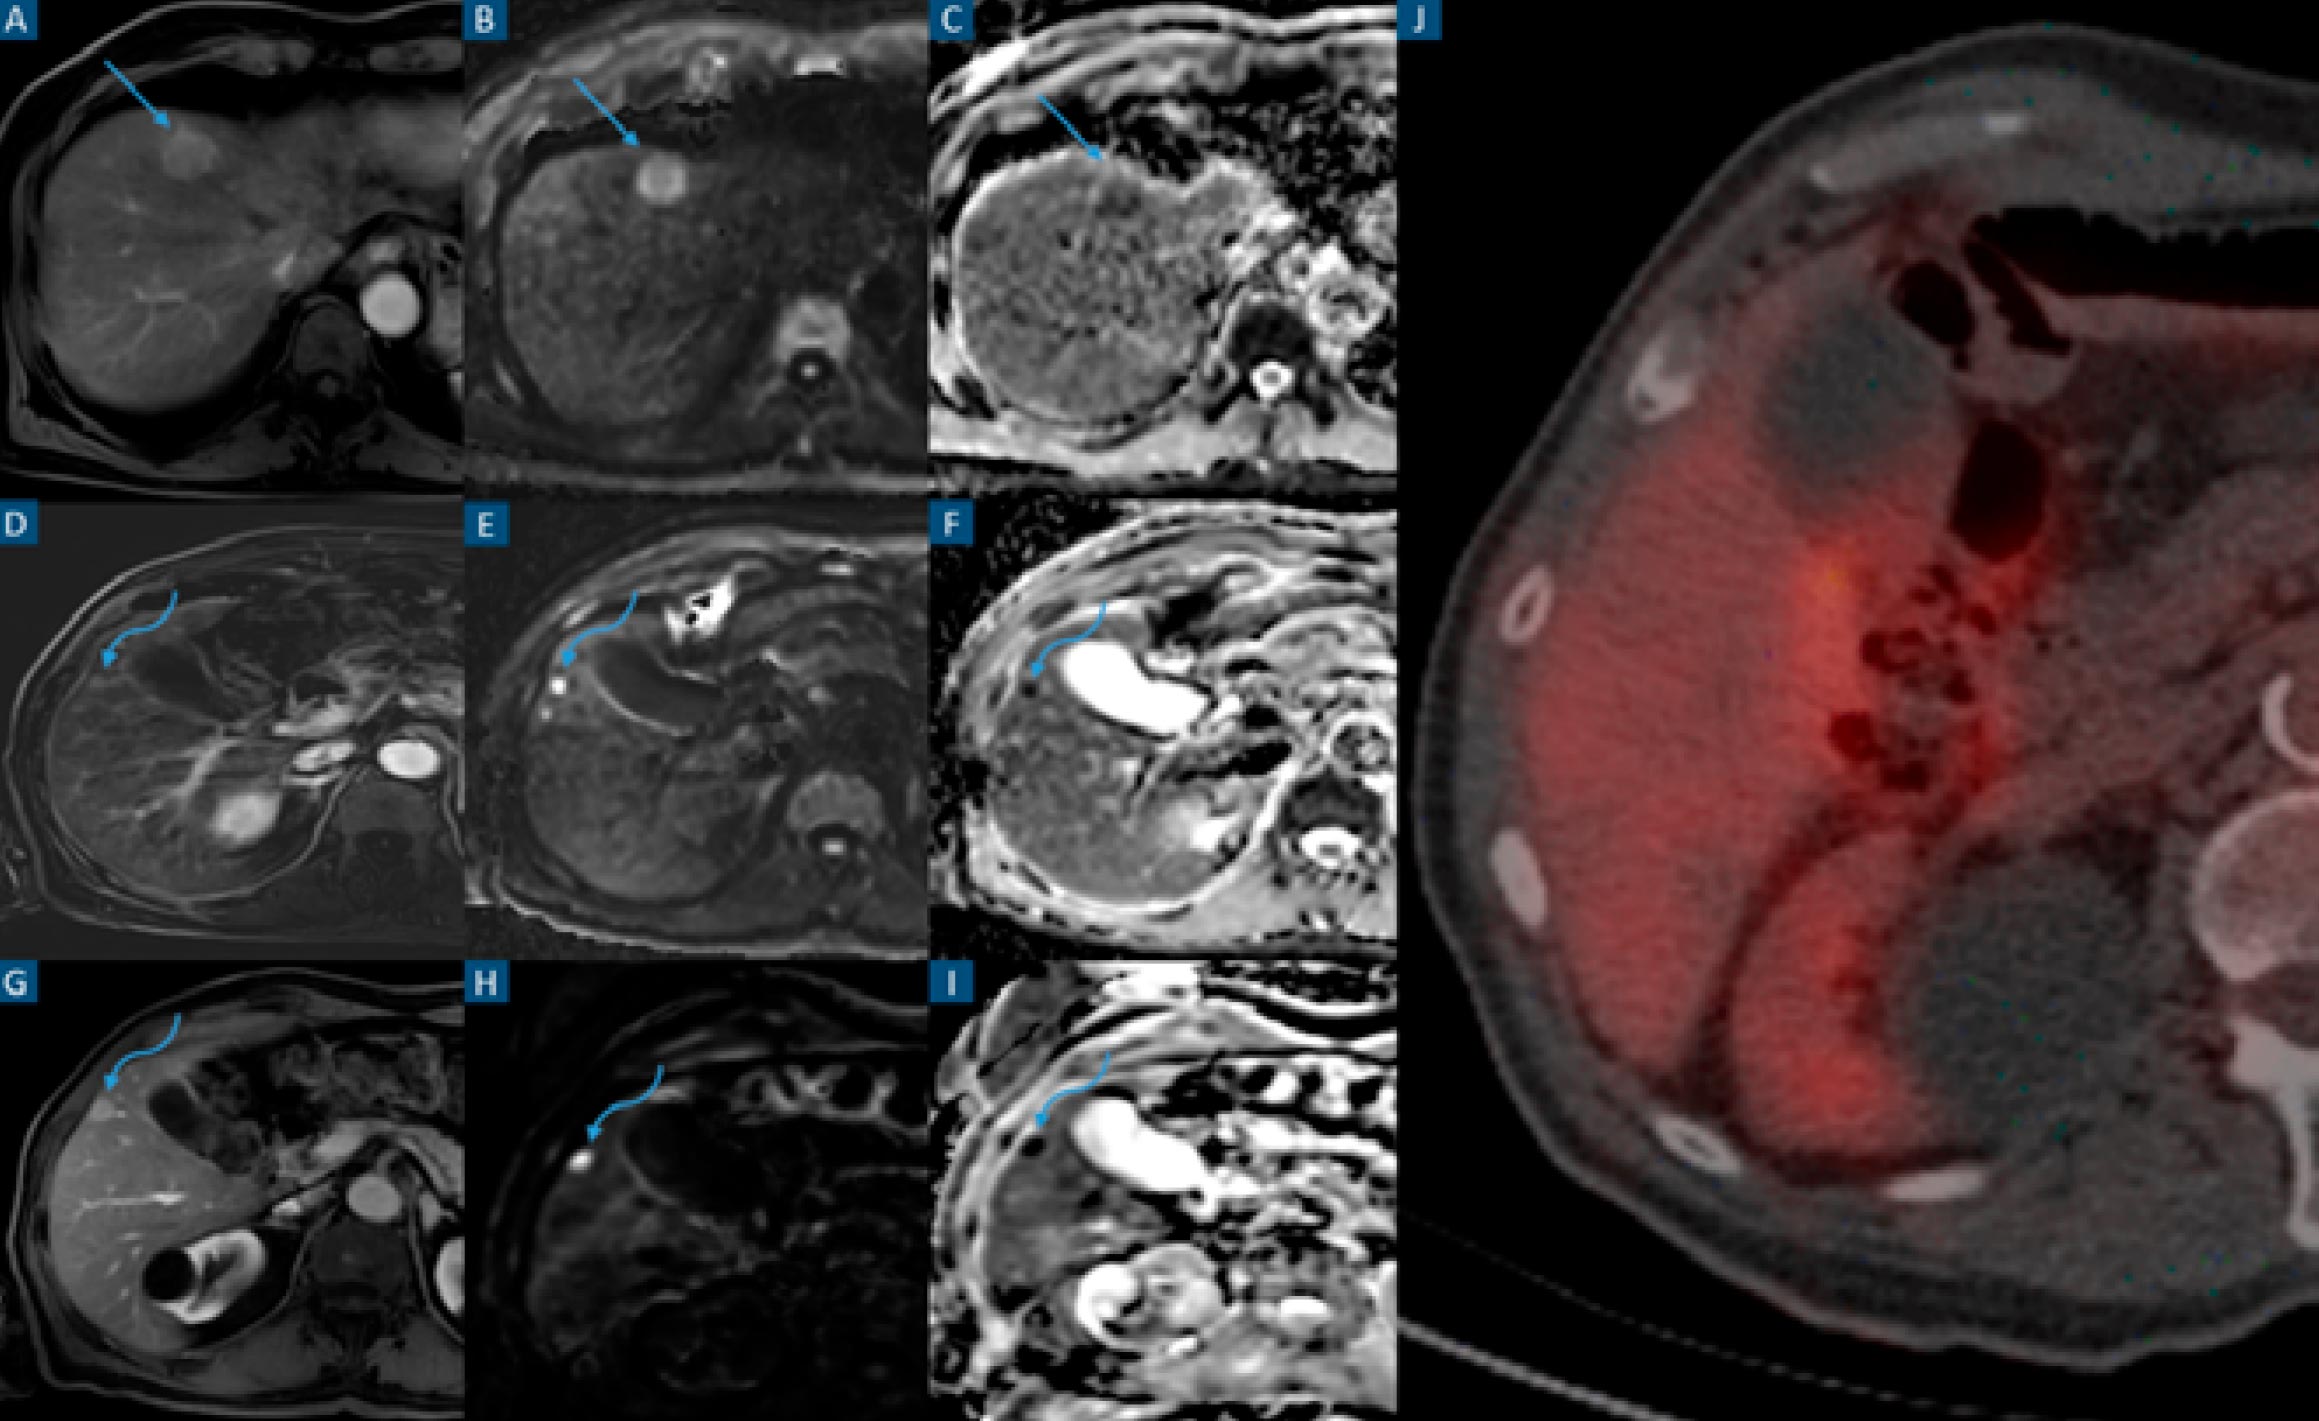

FIGURE 3: Liver metastasis undetected in intra-operatory hepatic ultrasound and PET-CT. Axial contrast-enhanced T1-weighted images on the arterial phase (A, D and G), and diffusion-weighted images at high b values (B, E and H) and ADC maps (C, F and I). Axial PET-CT with FDG (J). Patient with adenocarcinoma of the descending colon. Staging contrast-enhanced abdominal MRI was performed (A to F). A, B and C show a 20 mm highly restrictive hypervascular hepatic metastatic lesion in segment IVa (straight arrows). D, E and F show a 7 mm highly restrictive hepatic metastatic lesion in segment V (curved arrows). Intra-operatory hepatic ultrasound was performed only detecting the 20 mm lesion. Surgery consisting of a left hemicolectomy and single metastasectomy was performed. Histology revealed a metastatic adenocarcinoma lesion. Follow-up abdominal contrast-enhanced MRI performed 14 months later (G to I). G, H and I show an increase in size of the non-resected and previously described metastatic lesion in segment V (curved arrows). PET-FDG (I) acquired 3 days after the most recent MRI (G to I). No radioisotope uptake is detected in the previously mentioned lesion’s topography.